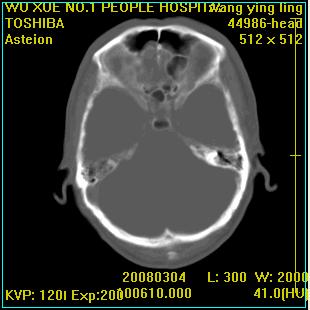

标题: CT12023:女,50岁,头部包块二月,伴轻微头痛,不伴发热。 [打印本页]

标题: CT12023:女,50岁,头部包块二月,伴轻微头痛,不伴发热。

这种病例还是比较多见,起源于颅骨板障,向颅内和颅外生长,考虑血管瘤或嗜酸性肉芽肿,要是有增强ct就好了。

多发溶骨性破坏,骨嗜酸性肉芽肿可能,转移瘤待排除,建议进一步检查。

时间短,考虑为转移瘤或骨髓瘤可能性大

颅骨多处破坏伴软组织肿块,考虑为转移瘤可能性大。